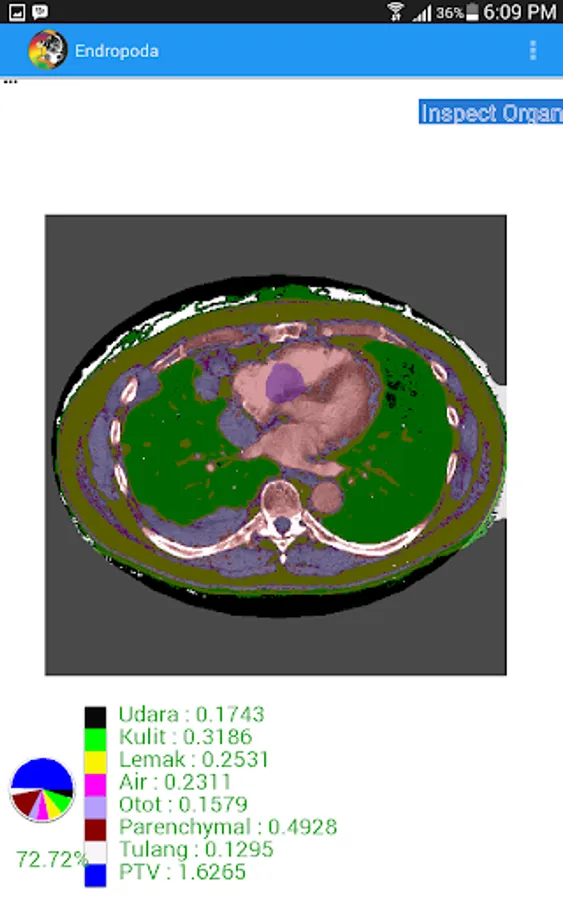

- Inspect Organ : The organ identification will be displayed automatically based on CT Number value that is stored in each pixel of CT-Scan image